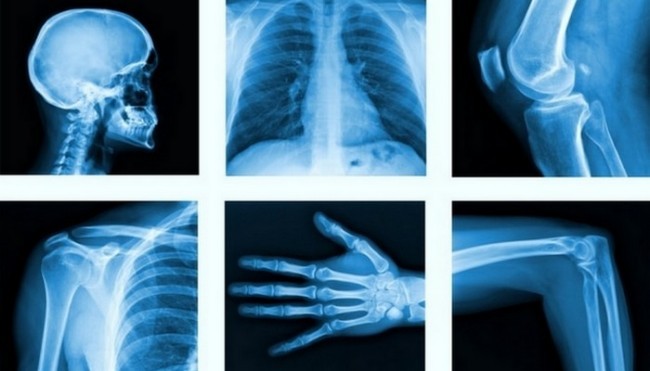

2. Rentgen

Bugungi kunda rentgen tasviri texnologiyasisiz suyak sinishi kabi travmalarga tashxis qo’yish va to’g’ri davolashni tasavvur qilish qiyin. Rentgen nurlanishi nemis fizigi Vilgelm Konrad Rentgen elektr tokini o’ta past bosimdagi gaz orqali o’tishini tadqiq qilinayotgan paytida tasodifan aniqlagan.

Olim bariy-platinotsianid bilan qoplangan elektron-nurli trubka qorong’ulashtirilgan xonada fluorestsent yorug’lik bilan yoritib turganini sezib qoldi. Katod nurlari ko’rinmas bo’lgani uchun u bunday yorug’likni qanday nurlar berayotganini bilmas edi va ularni rentgen nurlari deb atay qoldi. Olim o’z ixtirosi uchun 1901 yilda tarixda ilk bor fizika fanidan Nobel mukofotini olishga sazovor bo’ldi.